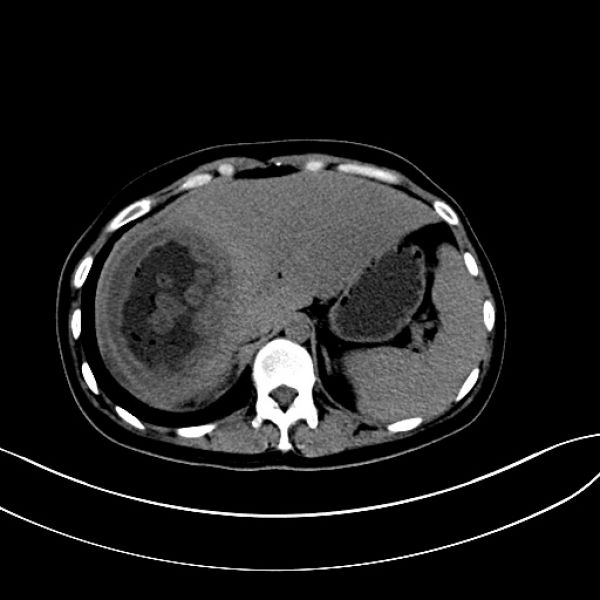

患者转入ICU治疗3天病情稳定后转湘雅医院继续治疗,并再次行肝创面压迫止血棉垫取出术,经积极治疗,患者恢复良好。治疗过程中两次行彩超引导下肝脓肿穿刺引流术,术后病情平稳,恢复出院。患者出院后,因肝脓肿反复住院数次进行脓肿冲洗引流,给患者生理和心理带来了很大影响。8月10患者以“肝脓肿穿刺引流术后3月余”来肝胆一科住院复查治疗,完善肝胆脾CT检查后发现,患者右肝脓肿仍然明显。王文儿主任组织肝胆一科医师进行科内讨论研究指出,通过仔细研究CT片及结合分析患者抢救治疗经过后认为要根治性解决患者目前病灶,必须行右半肝切除。经过与患者家属沟通,仔细说明患者目前病灶情况及治疗方案的利弊之后,家属充分了解并同意手术方案。经过充分术前准备后,于8月14日在全面插管下行右半肝切除+右隔下脓肿清除引流术,术后经积极治疗,患者顺利康复出院。

术前CT图像